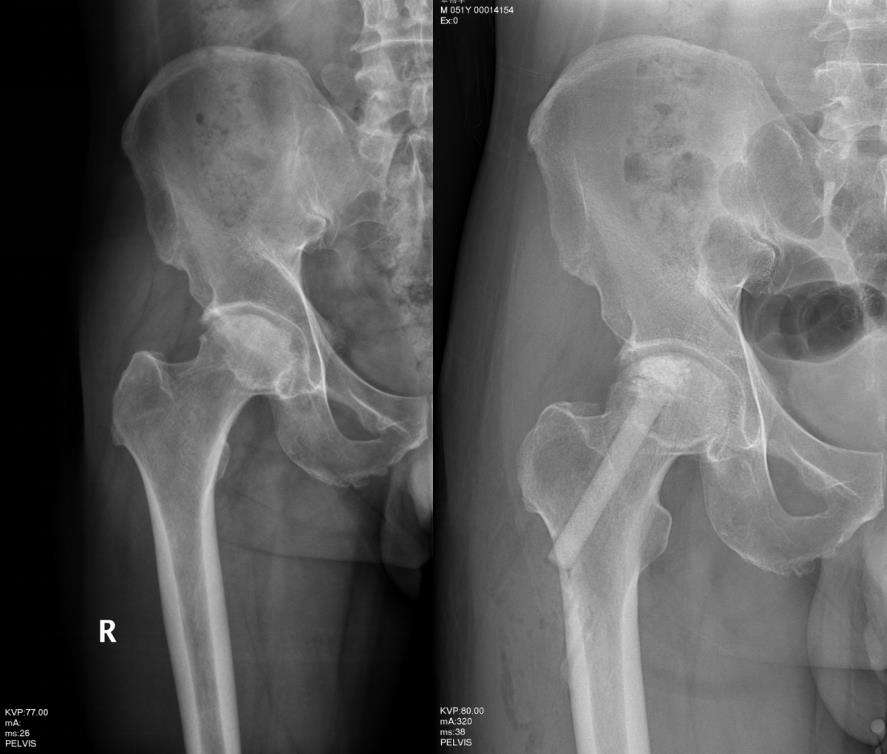

微创病灶清除陶瓷棒植入诱导血管重建治疗股骨头坏死,图为术前术后照片。